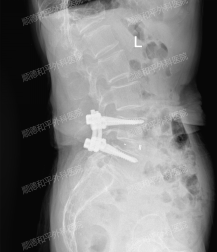

顺德和平外科医院:微创技术为75岁老人解除腰腿痛困扰

近日,顺德和平外科医院成功运用微创技术,为一位饱受腰腿痛折磨的75岁高龄女性患者,解决了困扰多年的腰椎疾病,显著改善了患者的生活质量。 该患者长期受腰痛困扰,近1个月来疼痛加剧,并伴有左下肢放射性疼痛,严重影响日常生活。自己在家躺着休息,吃镇痛药,效果都不是很好,晚上睡觉有的姿势下会痛醒。即使如此,吴阿姨内心还是不愿意到医院做手术,担心手术之后不能走路了,要卧床好几个月... 熟人介绍说顺德和平外科医院骨科二区(脊柱外科)张哉炯主任腰椎开刀很好,临床经验非常丰富,吴阿...